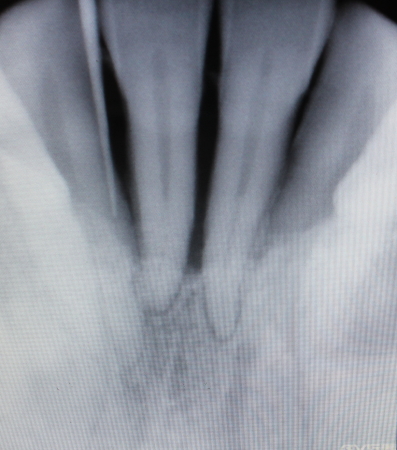

骨補填剤充填後のレントゲン写真